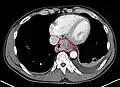

Speziell im Fall eines 3D-Datensatzes werden häufig Schnittbilder oder Schnittbildserien des Körpers errechnet. Die Orientierung der Schnittbildebene und die Position sind dabei meist frei wählbar. Im Gegensatz zu einem Projektionsverfahren wie der Durchstrahlung eines Körpers können so gezielt Details oberhalb oder unterhalb der interessierenden Schicht ausgeblendet werden. Im unteren Beispiel wurde durch die Technik der Schnittebene die störende Information der Rippen entfernt. Teilweise werden für die Diagnose oder Auswertung auch 3D-Rekonstruktionen erstellt, die sich beliebig im Raum orientieren lassen und Anblicke von allen Seiten erlauben.

Projektion (normale Röntgenaufnahme) -

transversales Schnittbild des Körpers